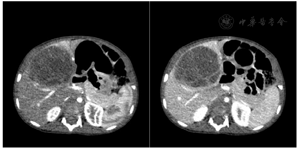

DECT采用选择性光子屏蔽(SPS Ⅱ)技术,在70kV和150kV的电压组合下实现能谱的显著分离。使用syngo.CT DE Virtual Unenhanced生成碘图/VNC融合图像,能显著提高血管和肿瘤的观察能力(图1和图2)。虚拟non-contrast(VNC)图像与常规平扫图像一致性匹配(图3),VNC可取代平扫,减少扫描次数做到降低总的剂量,提高合规管理和安全的儿童CT扫描使用。使用syngo.CT DE Monoenergy Plus,在这两个kV设置下获得的衰减值用于显示不同keV水平的图像。与在120kV下采集的常规CT图像相比,低keV的图像对比度显著增强,使得肿瘤侵犯的范围显示更加清晰(图4),低keV图像对比度是非常优异的(图5)。DECT的优势在于搭配西门子CT独有的水冷球管系统,双能力模式中两套球管独立工作,在同一辐射剂量的水平下,在不影响扫描流程和在不增加设备损耗的前提下,实现常规剂量成像,图像质量优异。70/Sn150kV的电压组合是目前用于儿童能量成像的最优参数设置。为了实现儿童低剂量能量检查,其他先进的技术也被使用,如CARE Dose 4D(实时自动曝光控制)和ADMIRE(高级模型迭代重建)。在本病例中,儿童多期CT检查,其中平扫、动脉期和静脉期用双能量技术,延迟期用自由呼吸大螺距技术,多期联扫总的辐射剂量仅为2.85mSv,为传统CT检查的2/5。